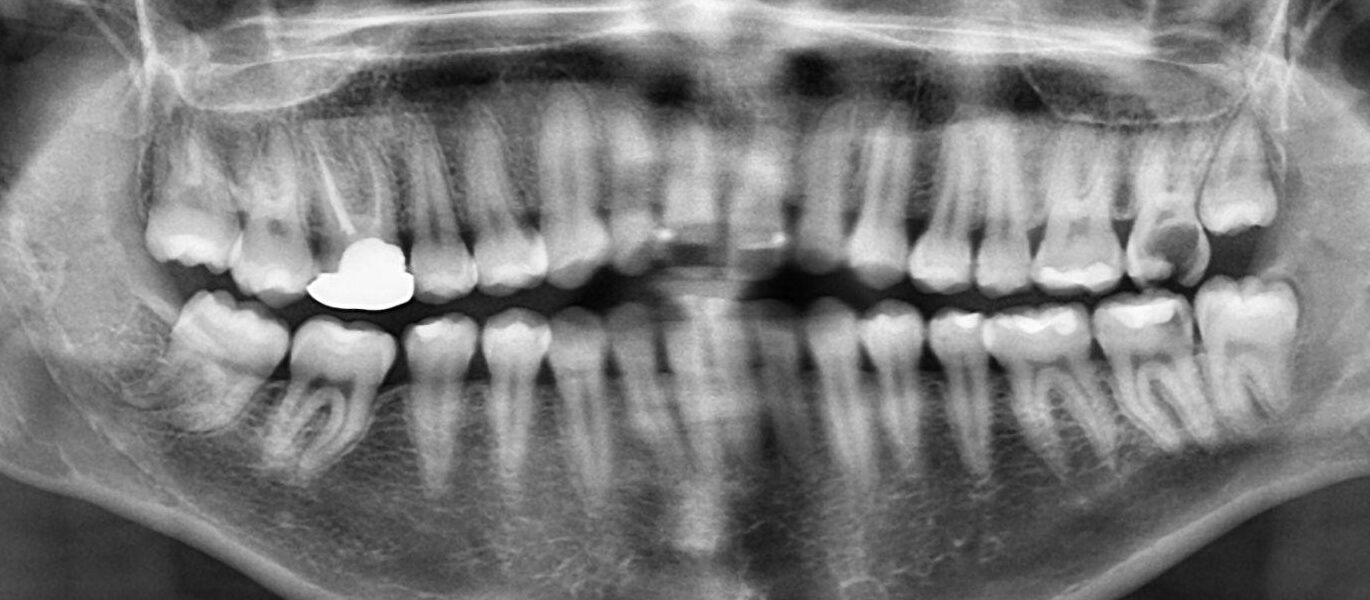

4. What option can be selected for upper jaw of this panoramic X ray?

5. What option cannot be selected for lower jaw of this panoramic X ray?

6. What option cannot be selected for this panoramic X ray?